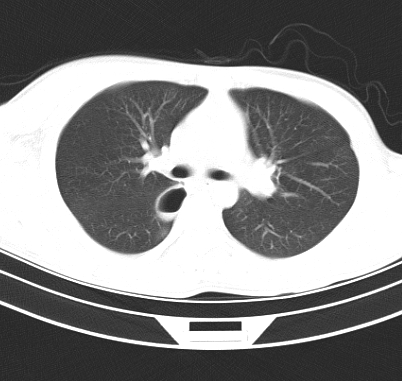

标题: CT19170:男 24岁,胸部外伤一周行CT检查 [打印本页]

男 24岁,胸部外伤一周行ct检查 未传纵隔窗

结合病史考虑肺挫伤后所致的肺气囊表现

结合临床考虑为右肺下叶背段撕裂伤。

首先考虑肺裂伤形成的液气囊肿.纵膈胸膜包裹性的液气胸可能性小,病变主要在肺内.

支持外伤性肺气囊。

肺撕裂伤液气囊形成

考虑外伤肺撕裂致右肺下叶纵隔胸膜下液气囊肿。

壁光滑完整,周围未见炎性灶及粘连带,考虑肺囊肿,不一定跟外伤有关!

结合临床考虑为右肺下叶背段撕裂伤后形成局限性包裹性的液气胸。

右肺下叶纵隔胸膜下液气囊肿,考虑肺囊肿?肺隔离症?